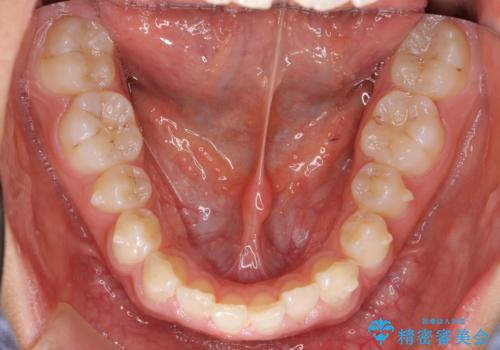

前歯のすきま 矯正治療とセラミックで小さな歯を形良く

- 前歯のすきまを気にして来院。

左上の2番が生まれつき小さく、スペースが余っていました。

右上の2番もやや小さめでしたが、相談の上、左上2番のみセラミックで形を整えることとしました。

そのほかの隙間はマウスピース矯正で閉じることにしました。